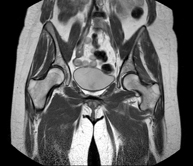

Prova diagnòstica no invasiva que consisteix en l'obtenció d'imatges d'alta definició anatòmica de la pelvis mitjançant l'ús d'un camp electromagnètic i ones de ràdio (amb un emissor i un receptor). No utilitza radiació ionitzant. Es realitza per a l'estudi de patologies d'úter, d'ovari, de trompes i de vagina, ja siguin d'origen tumoral, inflamatori o vascular. També permet valorar les estructures adjacents localitzades a la pelvis i la identificació de les seves alteracions. De vegades és necessari l'ús de contrast intravenós (Gadolini) per caracteritzar les lesions. - RM Pelvis masculina

Prova diagnòstica no invasiva que consisteix en l'obtenció d'imatges d'alta definició anatòmica de la pelvis masculina mitjançant l'ús d'un camp electromagnètic i ones de ràdio (amb un emissor i un receptor). No utilitza radiació ionitzant. No requereix preparació prèvia. En algunes ocasions necessita l'ús de contrast paramagnètic (Gadolini) per caracteritzar les lesions. Aquesta prova permet valorar òrgans com la bufeta urinària, la unió entre els urèters i la bufeta, la pròstata, les vesícules seminals, la uretra i els ossos de la pelvis, entre d'altres. - RM de Fetge